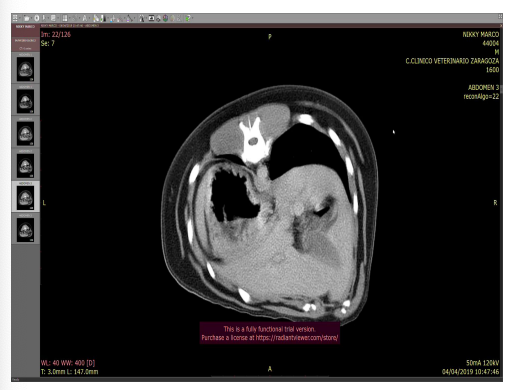

Topogradía abdominal del perro: Tac o TC del tejid blando, vista dorsal

Generalmente las imagenes de tac están espejadas